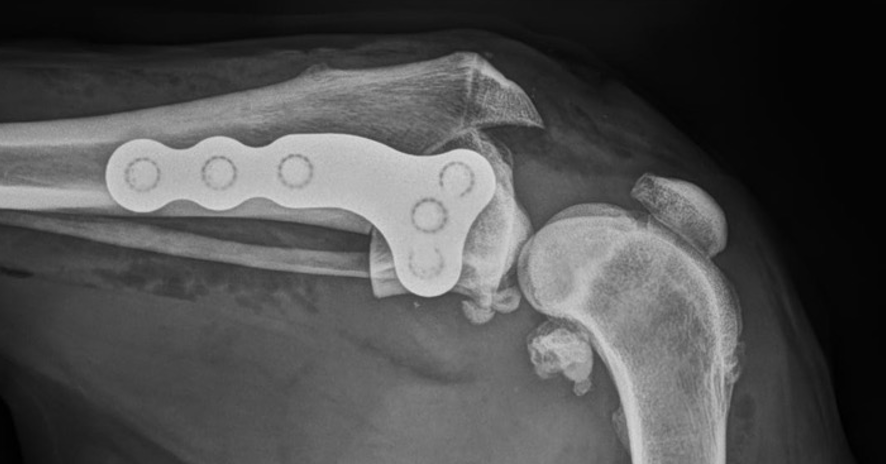

Joint surgery

Our joint surgery services

Diagnostic and therapeutic arthroscopy.

Cruciate ligament surgery, including tibial plateau levelling osteotomy (TPLO), and cranial closing wedge osteotomy (CCWO).

Patella luxation surgery, including including corrections of advanced level deformities and patella groove replacement.

Hip dysplasia assessment and surgery.

Angular limb deformity correction.

Total hip replacement using Biomedtrix implants

Canine unicompartmental elbow arthroplasty (CUE).

Arthrodesis.